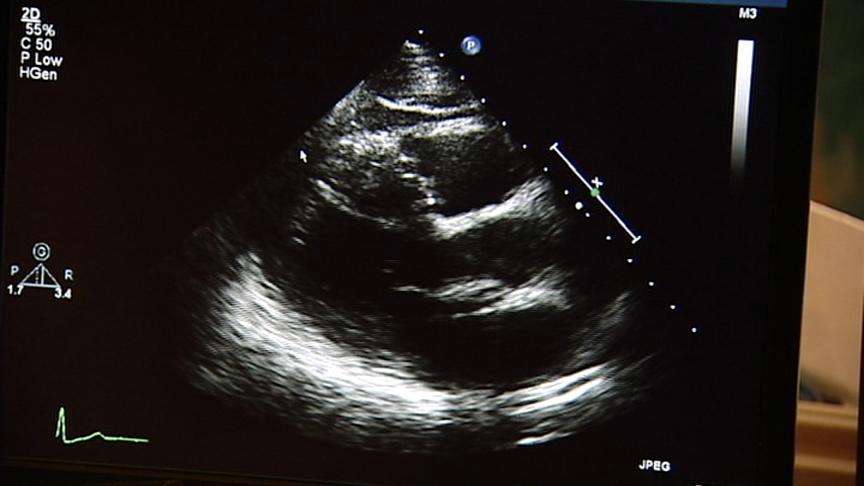

Doctors are using miniaturized internal ultrasound now to precisely fit stents inside clogged arteries, but the technology is about to take an even bigger leap.

That's because instead of a view from a miniaturized internal ultrasound device, doctors were relying on a traditional angiogram. But with the ultrasound probe, Casterella and his colleagues could see the stent was not fully expanded.

The team went back with a larger balloon and reopened it even more. Then they took more ultrasound pictures. It may not seem like much, but from 2.8 to 4.8 square millimeters, the fit was tighter and more precise, much less likely to trigger blood clots.